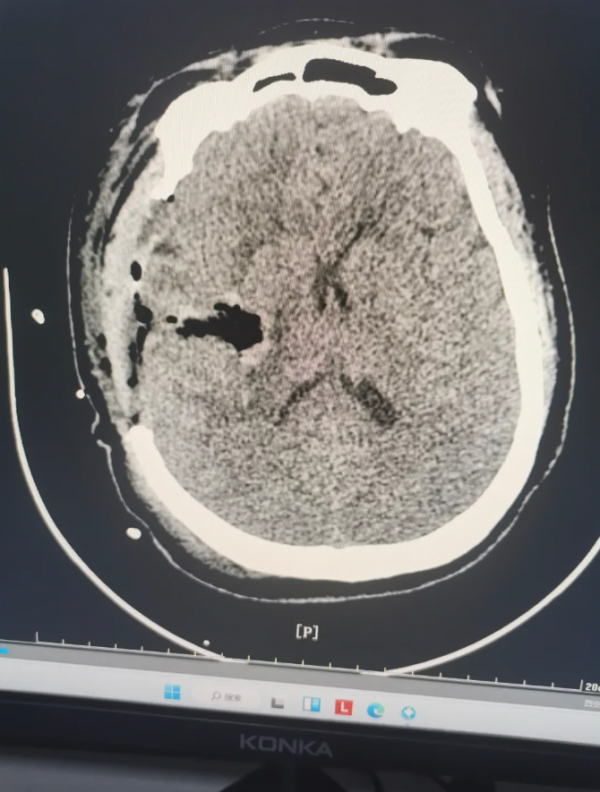

深夜,我院“120”接到急救电话,一名患者从床上跌落后出现左侧肢体无力、精神萎靡。急救人员抵达现场时,测得患者血压高达262/110mmHg,属极高危状态。紧急降压处理后,患者被快速转运至我院。急诊头颅CT检查显示:右侧基底节区急性脑出血,出血量达50ml,伴有明显脑水肿。患者随即被收入重症监护室(ICU)。

术后复查